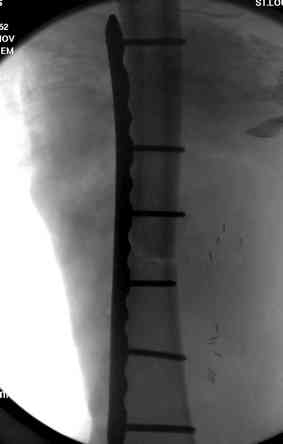

Огнестрельный дефект костей и передней группы мышц, поступил с юнилатеральным аппаратом, стабильность плохая, из раны обильное гнойное

отделяемое. #1;#2. Стержневой апп. снят, наложен апп. Илизарова, дренажно-ирригационная система промывки раны. #3; #4. После стихания инфекции,

аппаратом постепенно создана рекурвация для сближения контактов мышц (сухожилий) передней группы голени. #5;#6. Наложен шов на сухожлилия М.

Tibialis anterior и M extensor digitorum L. Одновременно компактотомия костей голени в В/3 для замешение дефекта костей. #7;#8. Постепенно

исправлена ось и возмещен дефект. В результате восстановление тыльной флекcии стопы и функции конечности. #9;#10;#11